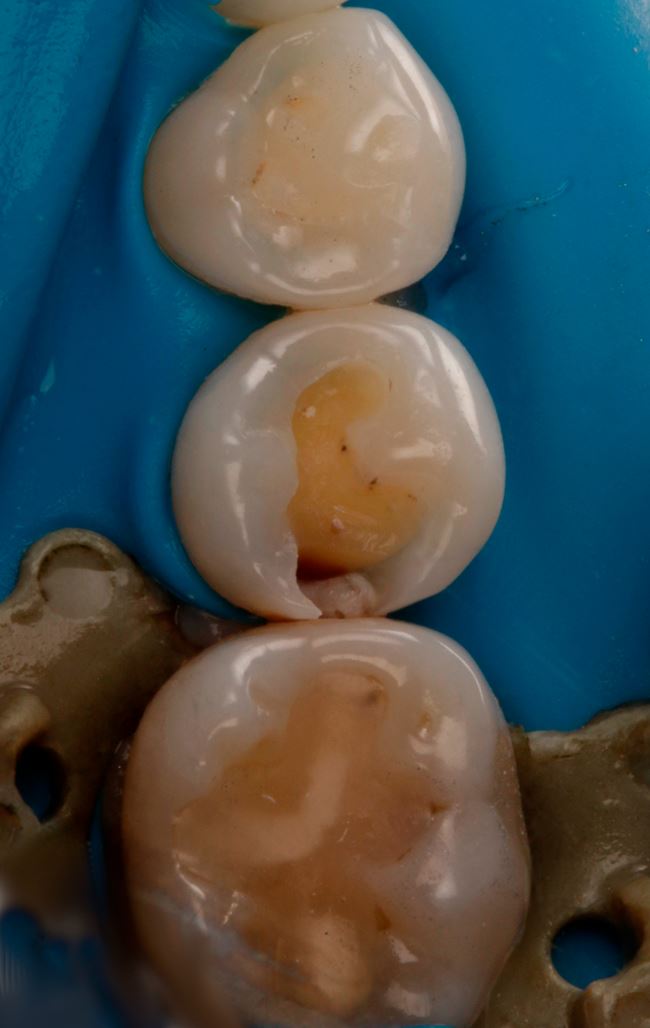

Ubytek na powierzchni dystalnej okazuje się całkiem duży, obejmuje znaczną część zębiny. Teraz nie ma już wątpliwości, że bez wypełnienia się nie obejdzie, a więc podajemy znieczulenie, zakładamy koferdam (ryc. 7) i przystępujemy do opracowania. Po usunięciu amalgamatu w dystalnej części ubytku widać ciemniejszą zębinę (ryc. 8). Usuwamy dystalną listewkę szkliwa i już widać wyraźne odwapnienie (ryc. 9). Dalej jest tylko ciemniej i głębiej (ryc. 10 i 11).

Ryc. 9. Ząb 45 po częściowym otwarciu ubytku.

Ryc. 10. Ząb 45 z częściowo opracowanym ubytkiem próchnicowym kl. II D.

Ryc. 11. Ząb 45 po opracowaniu ubytku kl. II D.

W przypadku zęba 45 wyraźnie widać, że DIAGNOcam się sprawdził, gorzej ze zdjęciem skrzydłowo-zgryzowym. Teraz pozostało już tylko założenie formówki (ryc. 11), wypełnienie ubytku, w tym przypadku nanohybrydowym materiałem kompozytowym Harmonize (Kerr) (ryc. 12 i 13), dostosowanie wypełnienia i wypolerowanie (ryc. 14). Chociaż to jeszcze nie wszystko. Ostatnią czynnością powinno być zmotywowanie pacjentki do codziennego stosowania nici dentystycznej. Obrazy z DIAGNOcamu świetnie się do tego nadają.

Ryc. 12. Ząb 45 po założeniu formówki jednościennej i klina.

Ryc. 13. Odtworzenie ściany stycznej w zębie 45 nanohybrydowym materiałem kompozytowym Harmonize Enamel A3.

Ryc. 14. Ubytek w zębie 45 bezpośrednio po wypełnieniu materiałem Harmonize Enamel A3.

Ryc. 15. Ząb 45 po leczeniu.